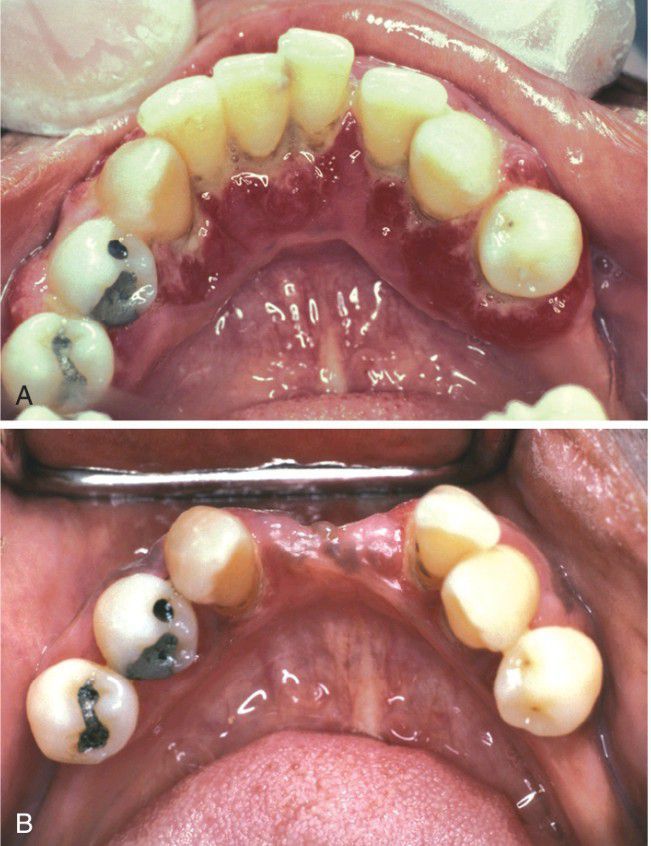

A, This diffuse, erythematous enlargement of the gingival tissues developed in a diabetic patient who discontinued taking her insulin. B, The gingival tissues have greatly improved after reinstitution of regular insulin injections. Several incisors were extracted because of severe periodontal bone loss.